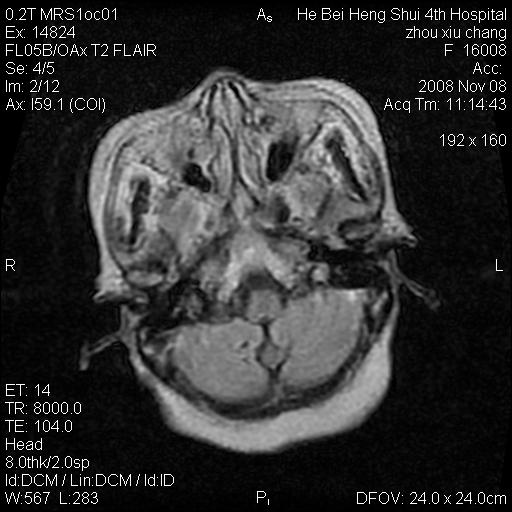

标题: MRI1883:女67岁,半年前曾患脑梗塞,治疗后好转,近3各月精 [打印本页]

女67岁,半年前曾患脑梗塞,治疗后好转,近3各月精神恍惚。

两种可能:1,转移瘤,2,脑炎,建议增强扫描

形态及整体病灶看起来首先考虑转移瘤或淋巴瘤,但奇怪的是多个病灶周围均未见显著的水肿区,这不符合这两个肿瘤的特点,结合ct表现及患者病史有个人考虑是否有皮层下动脉硬化性脑病伴多发胶质增生可能.

不像占位性病变,考虑脱髓鞘改变

皮层下动脉硬化性脑病伴脱髓鞘改变!